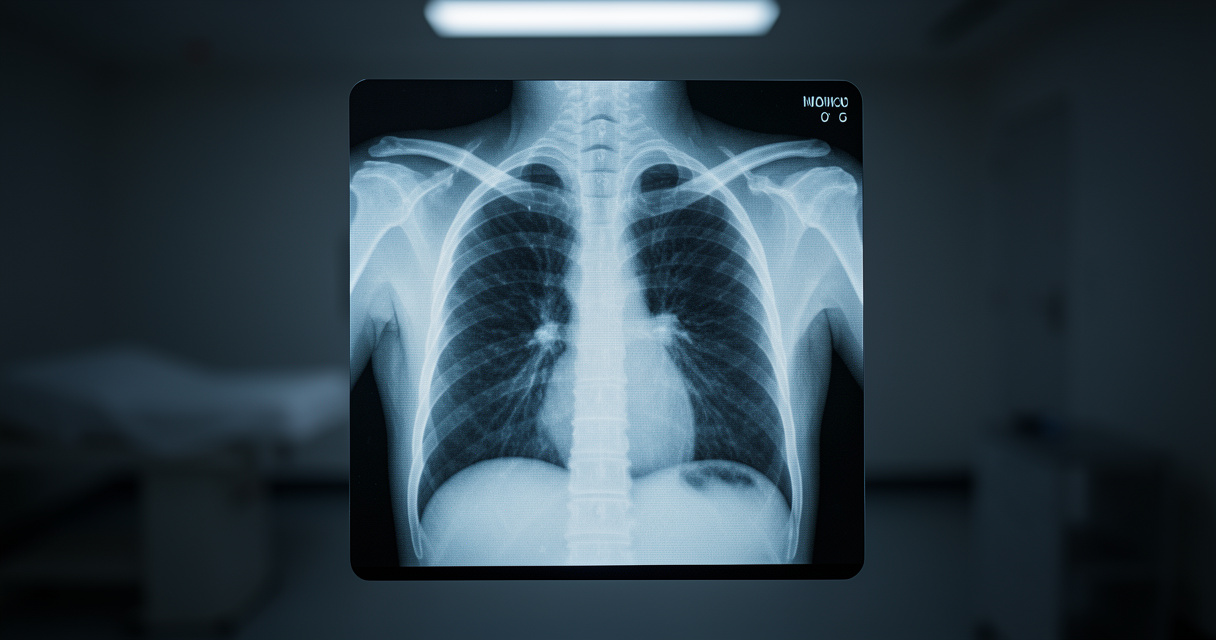

Sur le terrain, on parle souvent de l’IA comme d’un outil d’aide au diagnostic. Mais depuis quelques mois, une tendance inquiétante émerge des labos de recherche : l’IA générative est désormais capable de créer des radiographies deepfake si convaincantes qu’elles dupent à la fois les spécialistes et… les autres IA. Décortiquons ça.

En pratique, comment se déroule un tel test ? Des chercheurs ont constitué un batch mélangeant des clichés thoraciques et osseux réels avec des faux produits par des modèles comme ChatGPT-4o. Ils les ont soumis à un panel de radiologues de différents pays et niveaux d’expérience.